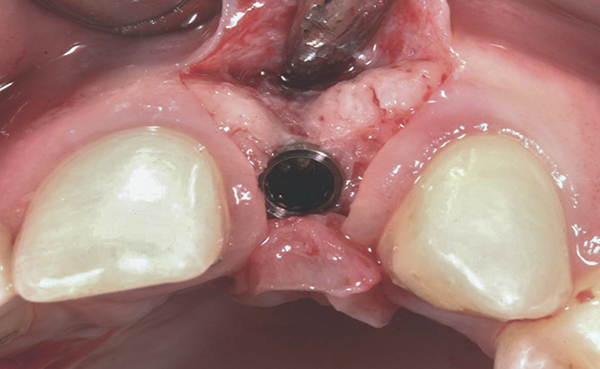

Fig 14. Implant placed into the thin ridge of bone, occlusal view.

Figure 14